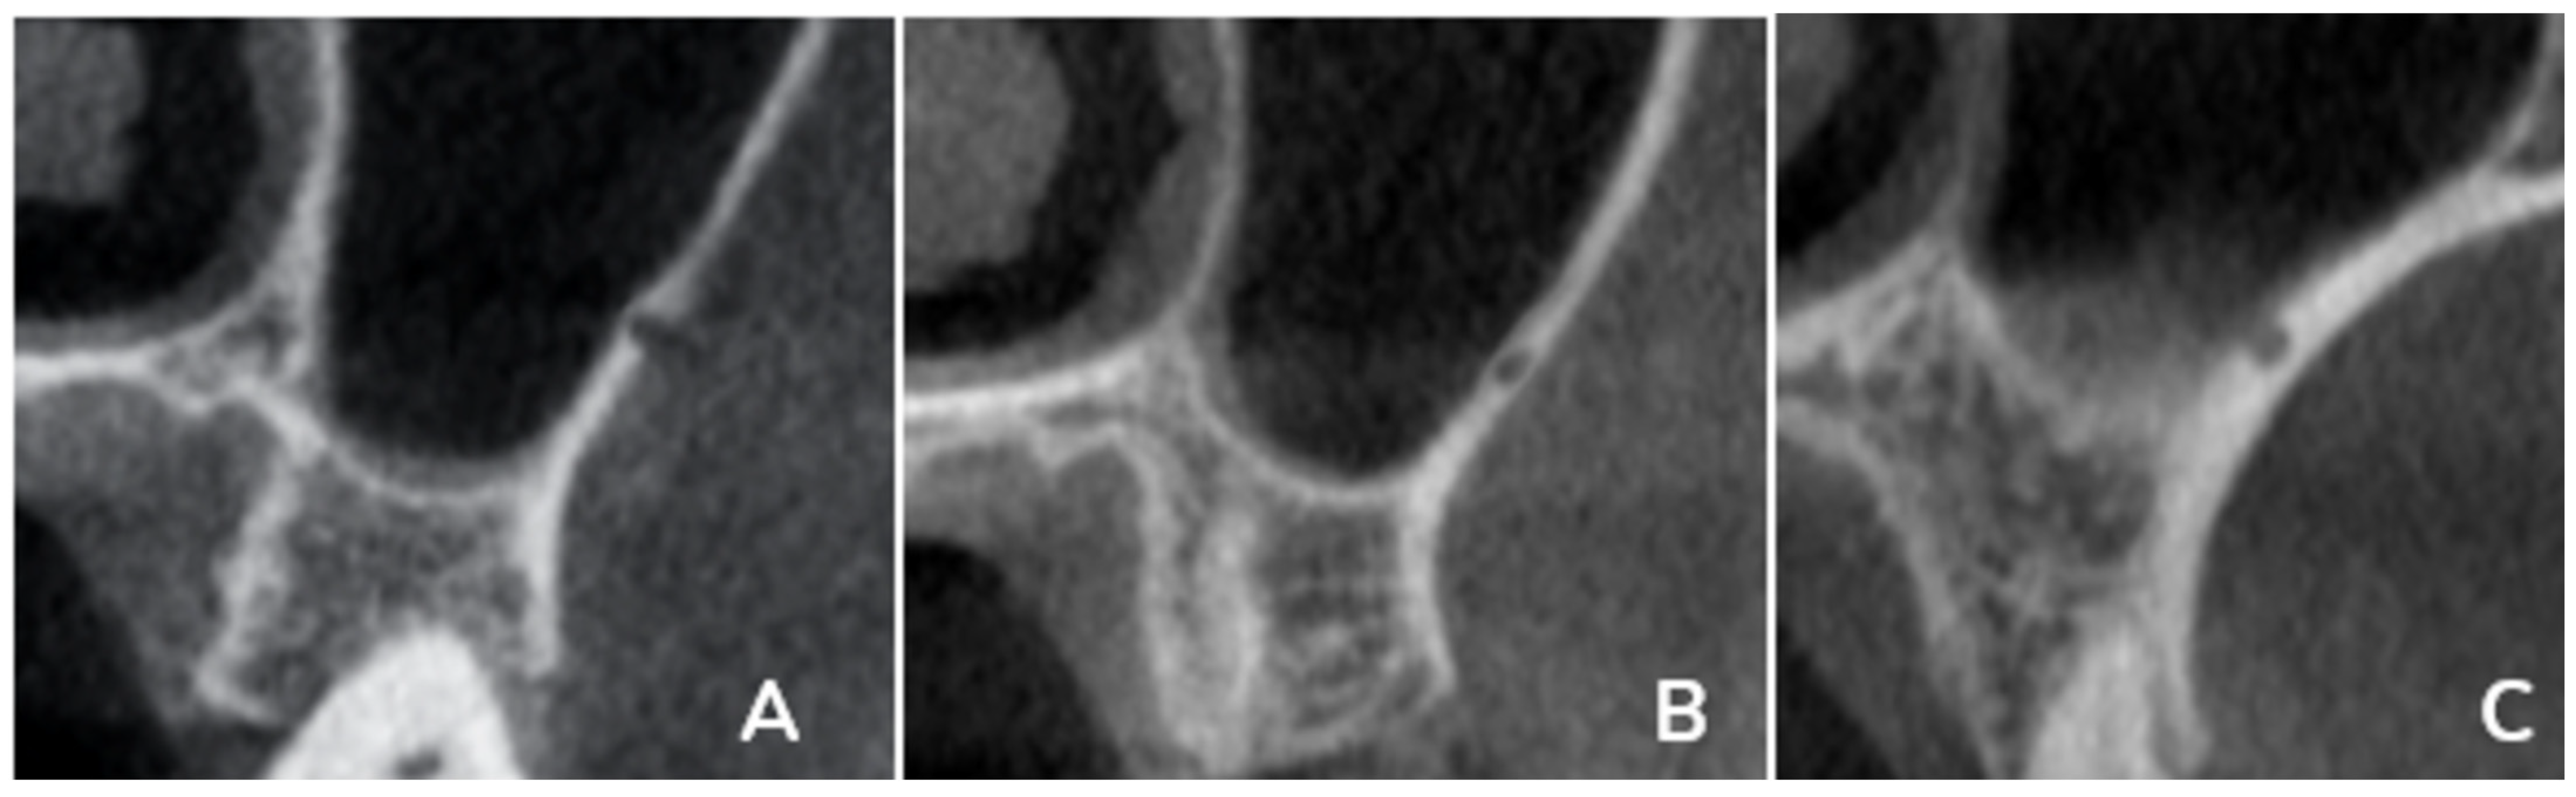

The primary outcomes of this study included multiple linear and categorical measurements obtained from coronal CBCT sections. These outcomes included measuring the fol-lowing in the coronal section: the distance from the artery to the (A) ridge crest, (B) floor of the maxillary sinus, (C) medial wall of the sinus, (D) height of the alveolar ridge, and (E) the diameter of the artery; finally, the presence or absence of the septa in the sinus (

Figure 1). Also, the PSAA’s anatomical location can be categorized as Type A (on the lateral sinus wall’s outer cortex), Type B (intraosseous), or Type C (beneath the Schneiderian membrane) (

Figure 2). All outcomes were recorded separately for premolar and molar regions based on root location or estimated axis in edentulous sites, as shown in

Figure 1 and

Figure 2.

The mediolateral position of the PSAA was categorized into three categories: A, the PSAA was found on the cortex of the lateral sinus wall; B, the PSAA was found intraosseous; and C, the PSAA was found below the Schneiderian membrane. For the premolar region at the right side, A was represented by 9.4%, B by 46.2%, and C by 41.9%, while the left side showed 5.1%, 53.8% and 38.5% for A, B, and C, respectively, with no significant difference between the right and left sides.

The molar region showed 6%, 35.9%, and 56.4% for A, B, and C, respectively, on the right side, and for the left sides, the values were 6%, 40.2% and 53%. While no significant difference was found between the right and left sides, the comparison of the position showed significant differences between the molar and the premolar regions, as shown in